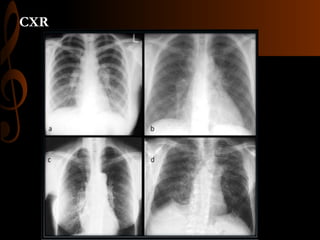

SCADDING SCALE CXR and HRCT CHEST

โ€ข Stage 1 (a) โ€“Bilateral hilar lymphadenopathy (55-90%)

โ€ข Stage 2 (b) โ€“Pulmonary infiltrates with BHL(40-70%)

โ€ข Stage 3 (c) โ€“ Pulmonary infiltrate alone (10-20%)

โ€ข Stage 4 (d) โ€“ extensive pulmonary fibrosis (10%)

CXR